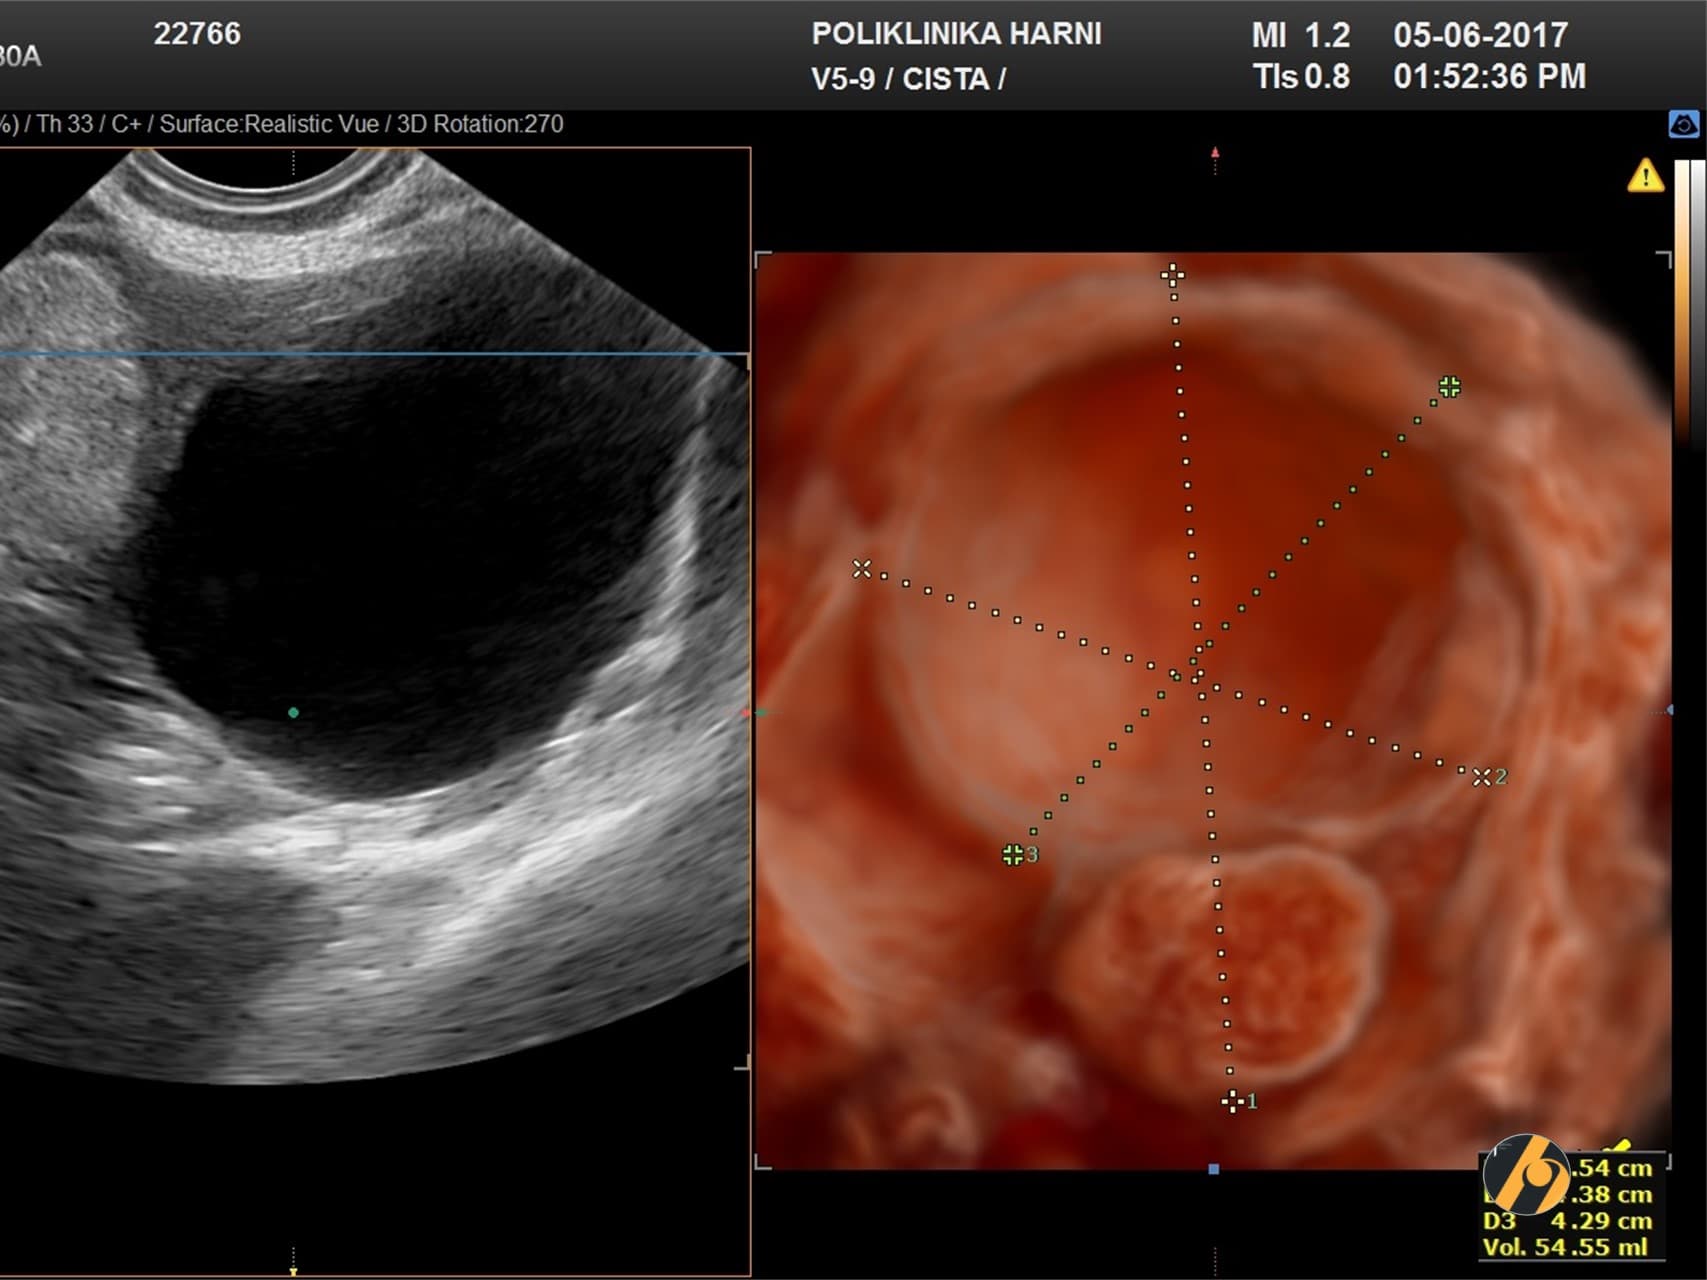

Najveća mudrost ultrazvučnog pregleda cista je odrediti njihovu prirodu, radi li se o funkcionalnim cistama kao što su folikularna i lutealna cista, koje se stvaraju tijekom svakog ciklusa iznova i spadaju u normalan nalaz, ili se možda radi o cistama koje nisu povezane s menstrualnim ciklusom. Ove ciste se nazivaju nefunkcionalne ciste i upravo je ultrazvuk jedna od najboljih metoda u predviđanju ponašanja nefunkcionalnih cista. Ultrazvukom se procjenjuje broj cista, postojanje intracističnih pregrada ili izraslina, postoji li slobodna tekućina u trbuhu. Doplerskim pregledom utvrđujemo vaskulariziranost, broj i raspored novih krvnih žila i mjerimo indekse protoka. Višedimenzionalnim rekonstrukcijama prikazujemo detalje koji nisu dostupni uobičajenom ultrazučnom pregledu.

Trodimenzionalni ultrazvuk (3D-UZV) uveden je u upotrebu devedesetih godina 20. stoljeća, a daje mogućnost prostornog, volumetrijskog i višepresječnog prikaza. Ovdje se dvodimenzionalni prikaz uz podršku kompjutora pretvara u trodimenzionalni prostorni prikaz, dok četverodimenzionalni ultrazvuk (4D-UZV) znači prostorni prikaz u stvarnom vremenu. Istodobni prikaz tumora u tri ravnine - uzdužnoj, poprečnoj i frontalnoj uz automatizaciju procesa i veći broj slojeva za bolji prikaz dubine i bolju dijagnostičku točnost, omogućuje ne samo mjerenje volumena i prikaz vanjskog izgleda tumora, te njegovog odnosa sa susjednim organima, već i usporedni prikaz unutrašnje stijenke tumora kao i intratumorskih promjena. Osim iznimne vrijednosti trodimenzionalnog ultrazvuka u procjeni urođenih grešaka ženskog reprodukcijskog sustava, novija istraživanja ukazuju na značajno veću dijagnostičku točnost 3D ultrazvuka u kombinaciji s 3D power doppler prikazom krvnih žila u prije operativnoj procjeni sumnjivog nalaza na jajniku.